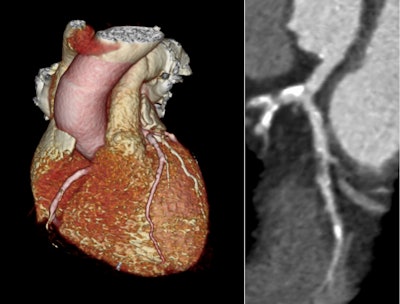

Example images from a coronary CT angiogram with 3D reconstruction and curved planar reconstruction of the left anterior descending coronary artery showing severe coronary artery disease. Courtesy of Prof. Michelle Williams and SCOT-HEART.

The SCOT-HEART trial explored the long-term benefits of using CCTA to guide care for patients with stable chest pain. Patients were divided into two groups: one received standard care with CCTA, and the other received standard care alone. After 10 years, those who had CCTA showed a significant reduction in the combined rates of coronary heart disease death and nonfatal heart attacks compared with those who did not have CCTA (6.6% vs. 8.2%). In particular, the CCTA group had fewer non-fatal heart attacks, highlighting the role of CCTA in improving patient outcomes.